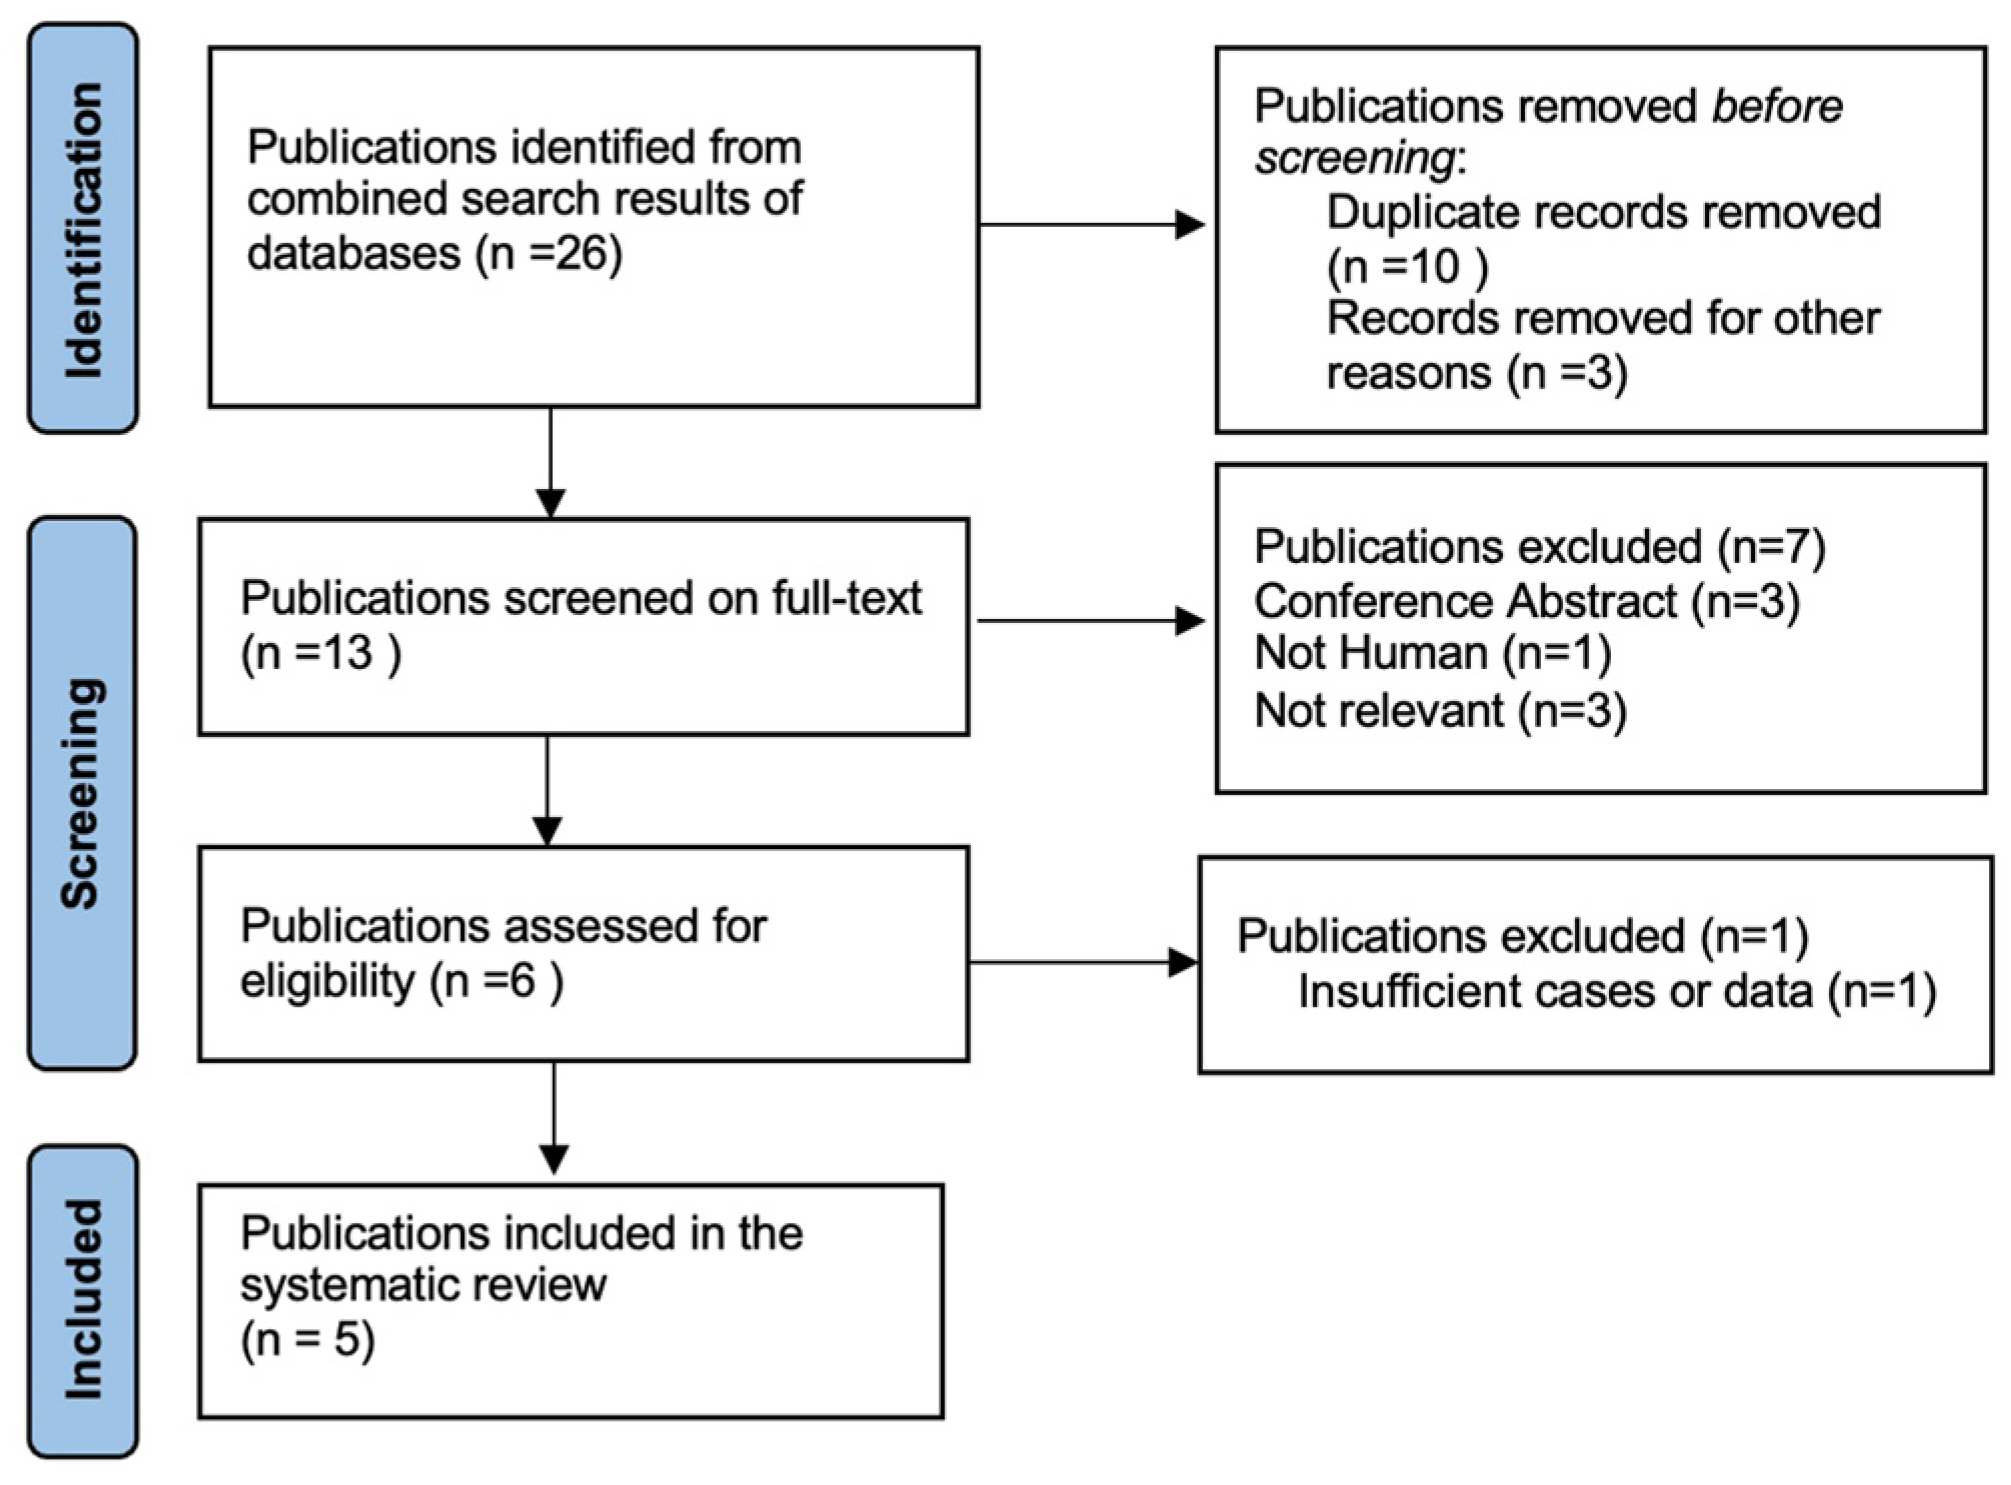

3. Materials and Methods

4.1. Study Inclusion and Characteristics of Included Studies